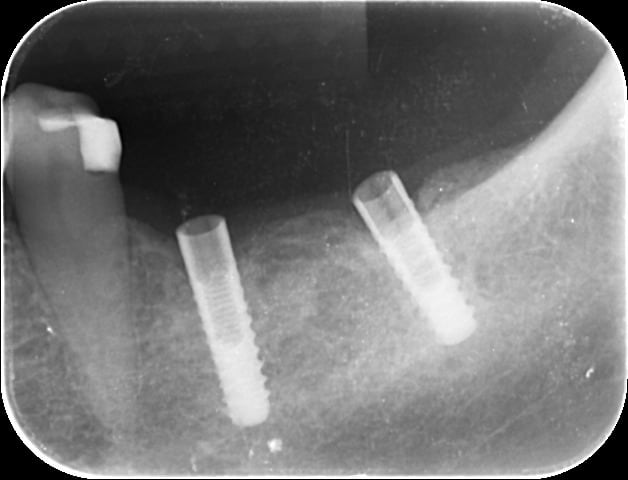

J'ai reçu en une patiente dont les 2 couronnes sur implants 36 et 37 solidarisées se soulevaient pas mal depuis quelques jours. J'ai un peu tiré dessus et j'ai récupéré, les deux CR avec un pilier dans la 37, et le pilier de la 36 est venu à part. Les piliers ne sont pas transvissés mais à priori impactés ( et peut-être scellés ?) directement dans l'implant. Le problème c'est évidemment qu'une fois sorti impossible de remettre les piliers en place. J'ai pas osé forcer...Peut-être qu'il faut un outil spécial ? Sinon les implants sont parfaitement ostéointégrés.

Et pas de bol, pas l'ombre d'une perte osseuse, Même pas le commencement ! ça m'aurait pourtant bien arrangé, mais là je me vois mal explanter ça...

Et voilà la fin de l'histoire. Après avoir sorti le pilier de la 37 avec la méthode de fotboy, grand nettoyage des pièces prothétiques. J'avais temporisé avec du Télio Onlay ( Ivoclar) dans le col des implants. Hier lors du RDV, nettoyage des résidus de ciment dans le fut des implants, et franchement heureusement que j'ai encore des tire-nerfs ! petite retouche sur une ou deux faces des hexagones des piliers(pas en titane) car le métal était légèrement déformé et ça rentrait plus. Et rescellement de l'ensemble.